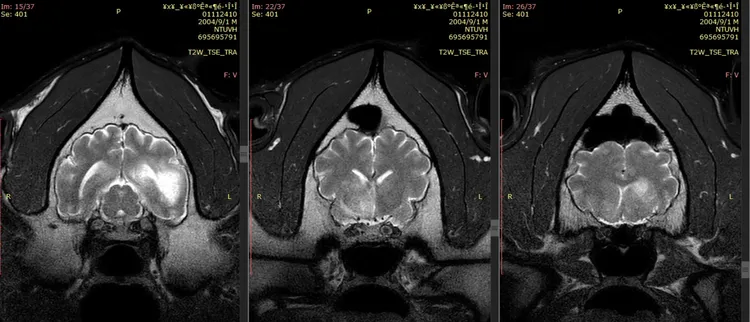

動物園今公布團團第2次MRI(磁振造影)檢查,影像中顯示團團腦部病變除既有病灶區域明顯擴大,且還出現腫塊效應,現在影響到神經元,惡性腫瘤機率大幅提高但未能進行侵入性切片檢查,故無法百分之百確認。

團團第2次MRI(磁振造影)檢查結果出爐。動物園提供